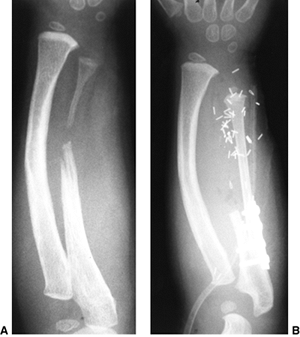

![]() |

Figure 23.8 A:

Preoperative radiograph of a congenital radioulnar synostosis. There is complete fusion of the proximal radius and ulna, and posterior dislocation of the radial head. The entire ulna is mildly hypoplastic. B: Postoperative radiograph of a derotation corrective osteotomy for this patient. A longitudinal wire is passed down the medullary canal of the ulna across the synostosis site. This Kirschner wire starts from the proximal ulnar apophysis. The osteotomy cut is performed through the synostosis. The transfixing wire is obliquely placed to secure the corrective derotation to a position of 0 to 20 degrees of pronation. |